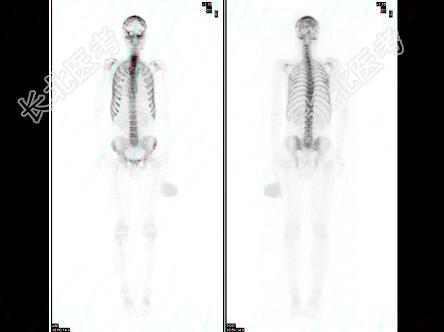

多项选择题男性,62岁, 膀胱印戒细胞癌术后半年,全身酸痛, 对骨显像地描述正确的是 ( )

A、颅骨多个“轮圈征”,提示有溶骨性病变

B、脊柱骨、肋骨弥漫性均匀性浓聚,肾脏不显影,是“超级骨显像”

C、提示中轴骨广泛转移癌

D、该患者预后不良